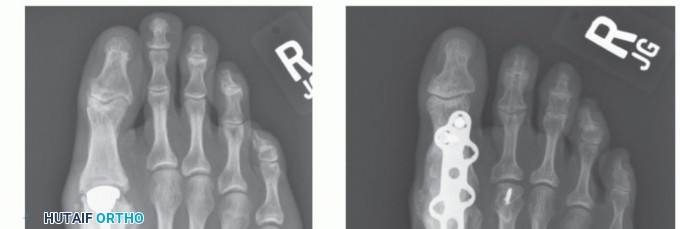

Radiographic grading system: The radiographic grading system often used in the literature,7 grades 1, 2, and 3, signify the percentage of joint space narrowing, the presence or absence of subchondral sclerosis or subchondral cyst, and the degree of osteophyte formation (Table 1; FIG 4).

FIG 4 • A. Grade 1 hallux rigidus. B. Grade 2 hallux rigidus. C. Grade 3 hallux rigidus. D. Lateral view of hallux rigidus.